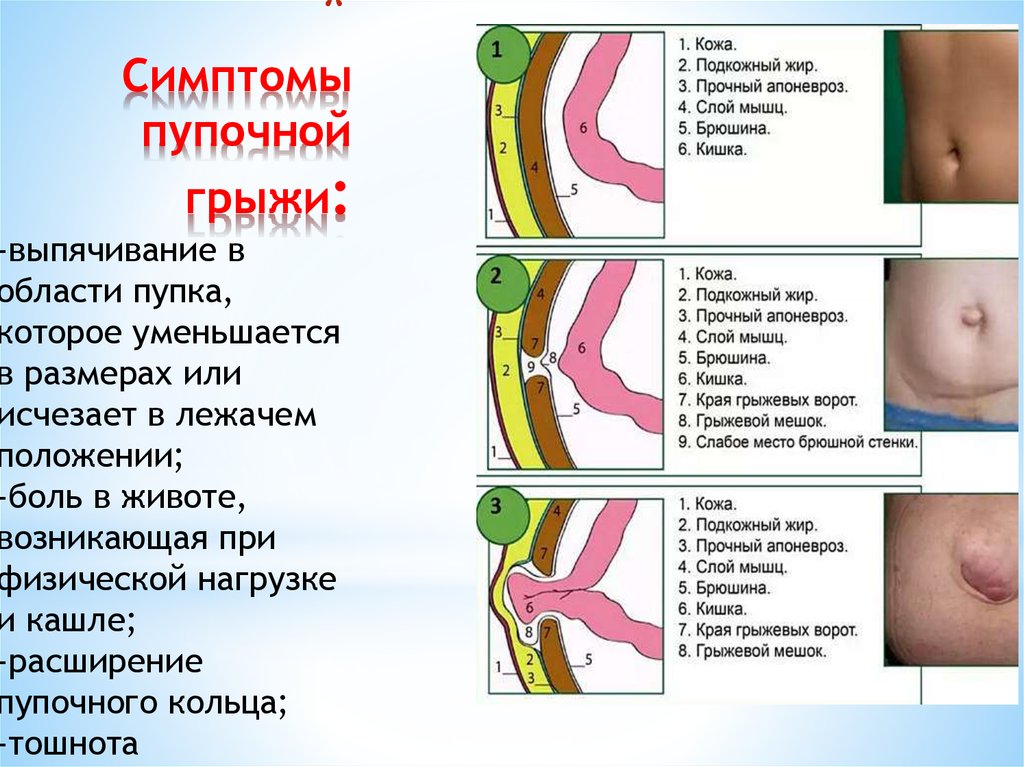

Пупочную грыжу можно распознать по следующим признакам:

- Выпячивание увеличивается, если малыш тужится. Его сильнее видно, когда ребенок стоит;

- В грыжевом мешочке может находиться часть кишечника, тогда во время ощупывания можно ощутить урчание. При большом размере грыжи заметно шевеление кишечных петель;

- Мышцы живота расходятся.

Чаще всего грыжа возникает вследствие дефекта передней брюшной стенки, слабости пупочного кольца. Провоцирующим моментом является длительное повышение внутрибрюшного давления в результате сильного кашля, запоров, продолжительного плача. Такие заболевания, как рахит, гипотрофия, снижающие тонус мышц, создают благоприятные условия для образования пупочной грыжи. Наиболее часто грыжа встречается у недоношенных детей. В пупочную грыжу обычно выпадают петли кишечника ребенка или сальника.

Самое частое объяснение того, что у ребенка может выпятиться пупок, – это грыжа. Обычно она носит врожденный характер и становится заметной на втором месяце жизни крохи. В норме после обрезания пуповины пупочное кольцо стягивается, сжимается. Если этого не происходит, или оно не закрывается до конца, формируется выпячивание. Особенно оно заметно, когда ребенок плачет или кашляет. Любое напряжение мышц живота выдает грыжу. Причем в обычном состоянии, когда малыш лежит, он спокоен, она может и не выдавать себя.

Пупочная грыжа у новорожденных может быть прямой или косой. В первом случае грыжевой мешочек и его составляющие просто выходят за пределы пупочного кольца. Во втором — возникает более сложная структура: грыжевой мешок сначала оказывается в просвете между поперечной фасцией и белой линией живота, а затем выводится в пупочное кольцо.

Грыжа у новорожденного как правило бывает «мобильной» и легко вправляемой в пупочное кольцо. Правда, и невправляемые, неподдающиеся грыжи тоже иногда встречаются, хотя и нечасто. Пупочное кольцо в норме бывает эластичным и широким, поэтому и грыжевой мешочек свободно перемещается внутрь и наружу. Если кольцо узкое, то подвижность грыжи значительно снижается.